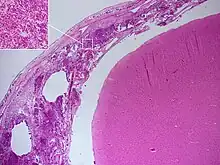

Postmortem

Meningitis can be diagnosed after death has occurred. The findings from a post mortem are usually a widespread inflammation of the pia mater and arachnoid layers of the meninges. Neutrophil granulocytes tend to have migrated to the cerebrospinal fluid and the base of the brain, along with cranial nerves and the spinal cord, may be surrounded with pus – as may the meningeal vessels.[57]